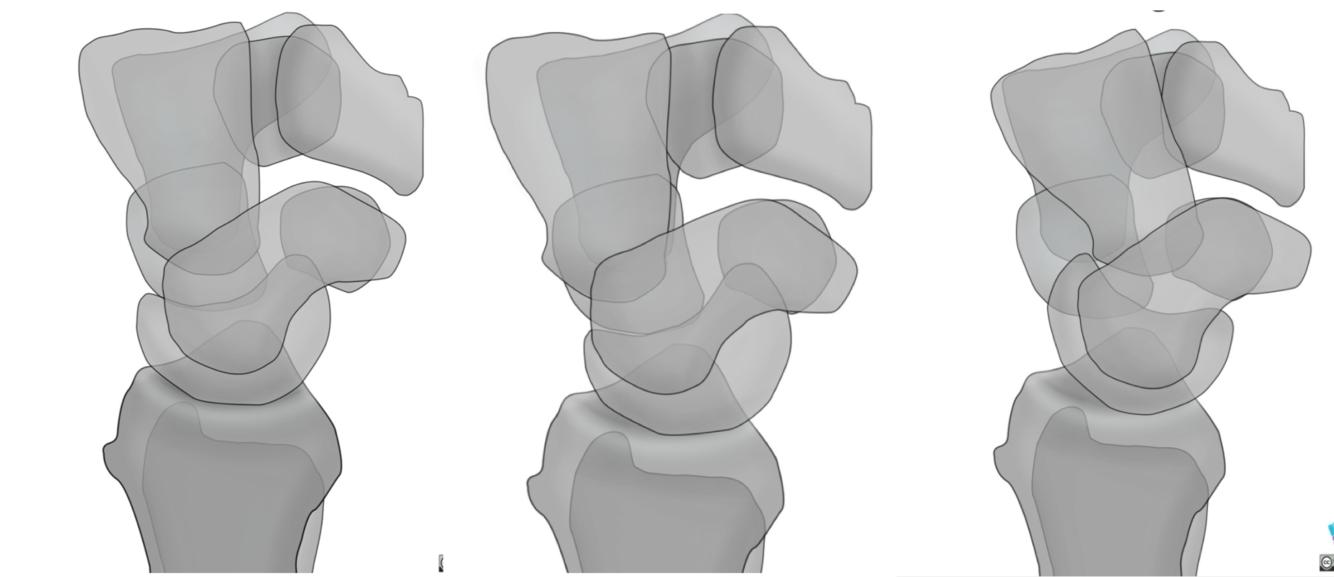

Name each alignment show in the picture

Scapholunate angle in DISI

Scapholunate angle > 60 deg

Normal scapholunate angle

30-60 deg

Scapholunate angle in VISI:

<30 deg